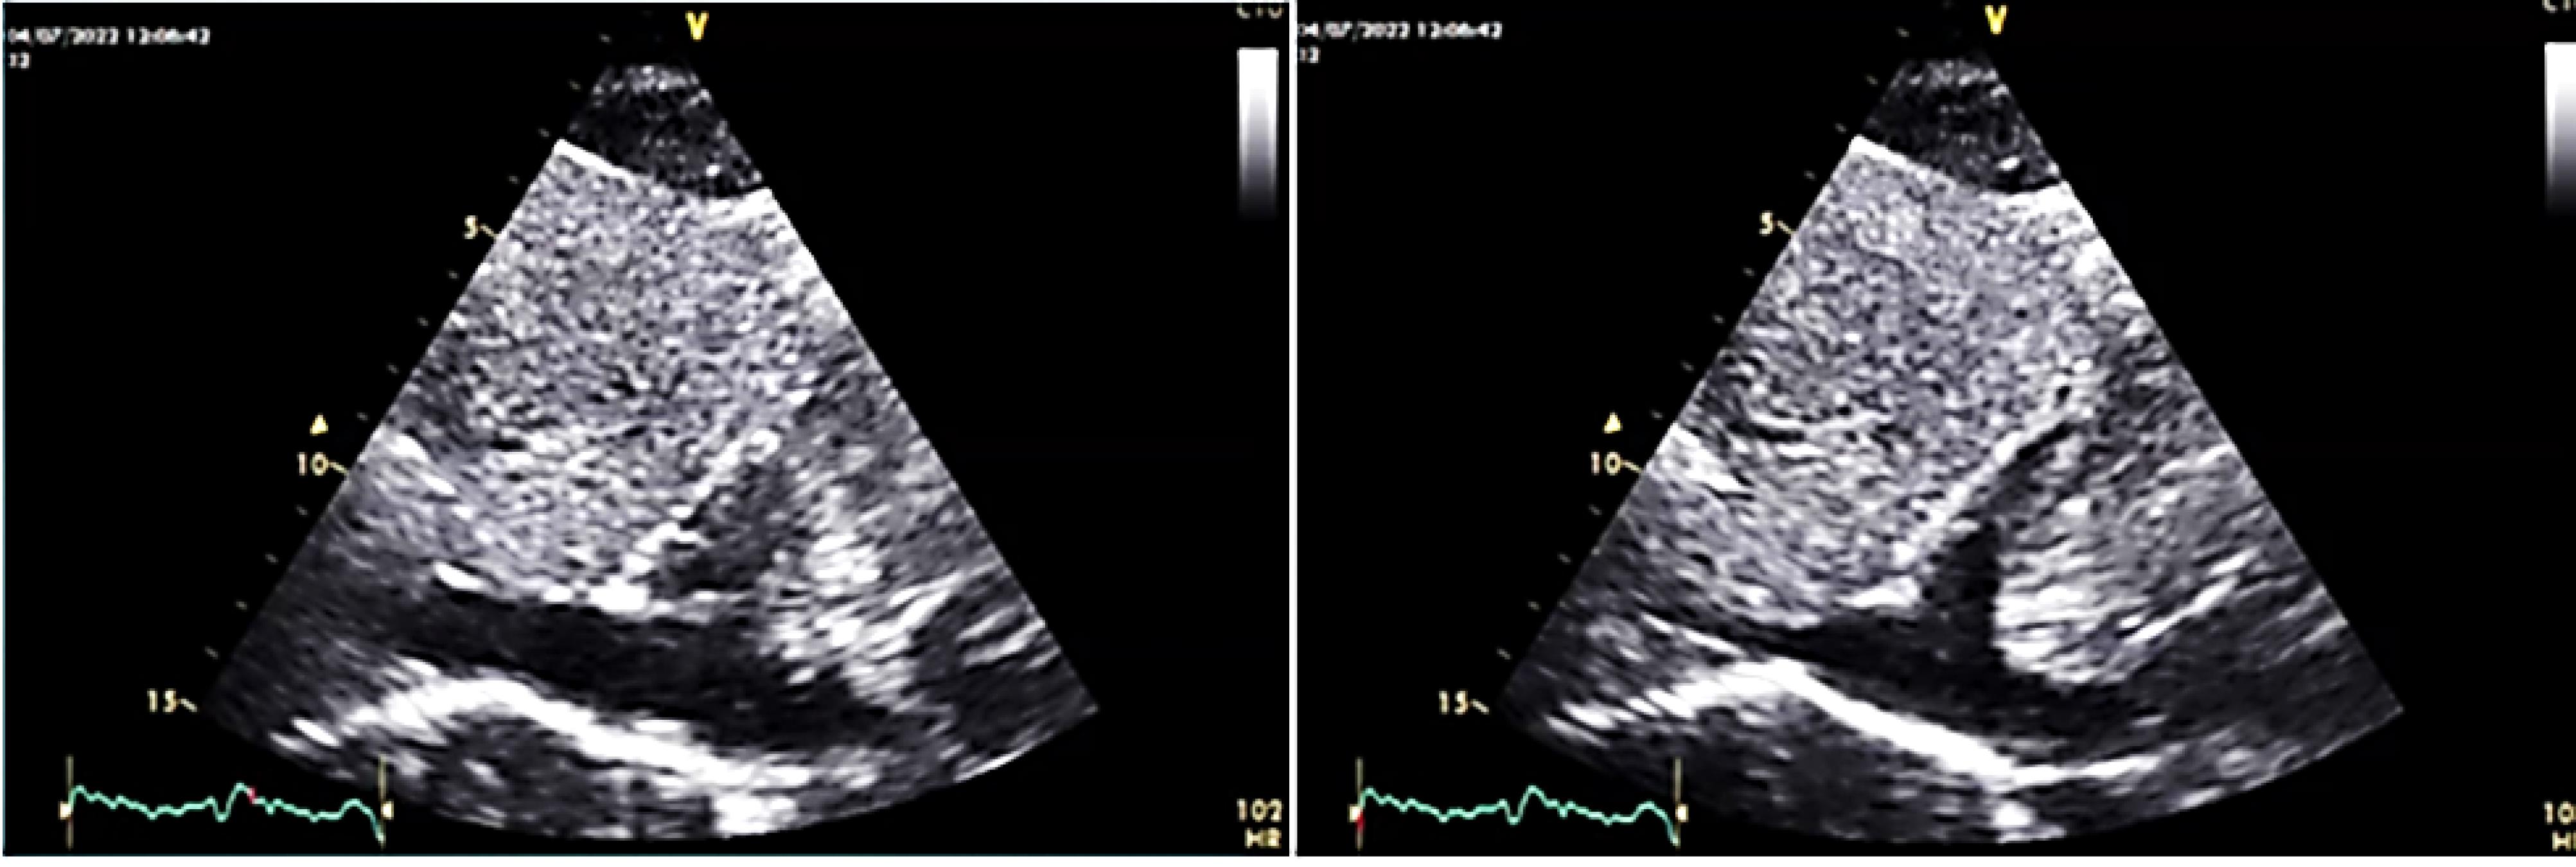

On transthoracic echocardiography a large size mobile pedunculated round-shape mass (5.9cm*3.3cm) in right atrium attached to inter-atrial septum at foramen oval level was detected (Figure 1).

Figure 1.

large size round shape mass in RA on TTE

The mass was none homogeneous and several filamentous apparatus was detectable on mass’s surface on echo. In cardiac cycle intermittent protrusion of mass into the TV and dynamic TV stenosis results in cyclic IVC dilation (Figure 2).